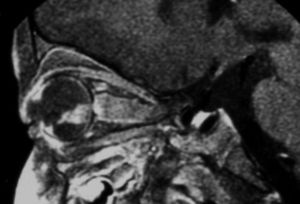

전통적인 초음파 B-스캔은 종양 내 석회화를 감지할 수 있으며, 고주파 초음파 B-스캔은 기존 초음파보다 더 높은 해상도를 제공하고 종양과 눈 앞부분의 근접성을 확인할 수 있다. 자기 공명 영상(MRI)은 시신경 침범, 맥락막 침범, 공막 침범, 두개내 침범과 같은 고위험 특징을 감지할 수 있다. 전산화 단층 촬영(CT)은 방사선이 RB1 유전자 돌연변이 환자에게서 더 많은 눈 종양의 형성을 자극할 수 있으므로 일반적으로 피한다.[37]

안저 소견, CT, MRI, 초음파 진단 등으로 확진한다.